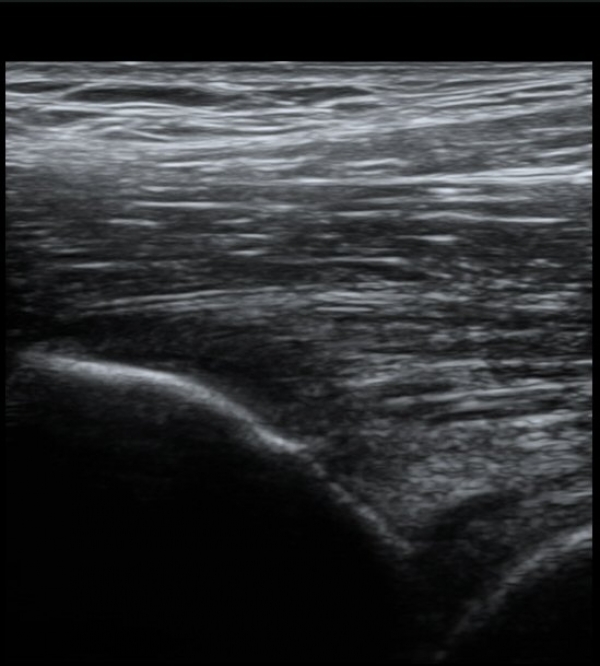

´ëÅðÁ÷±Ù ÈûÁ٠Ⱦ´Ü¸é °Ë»ç¿¡¼­µµ ÈûÁÙÀÇ Àú¿¡ÄÚ º¯È­¸¦ º¸À̰í(»çÁø 4, 5) ÀÌ º´Àû º¯È­µµ

°ÇÃø(»çÁø 6, 7)°ú ºñ±³ÇÏ¸é ½±°Ô ÆÇ´ÜµÈ´Ù.